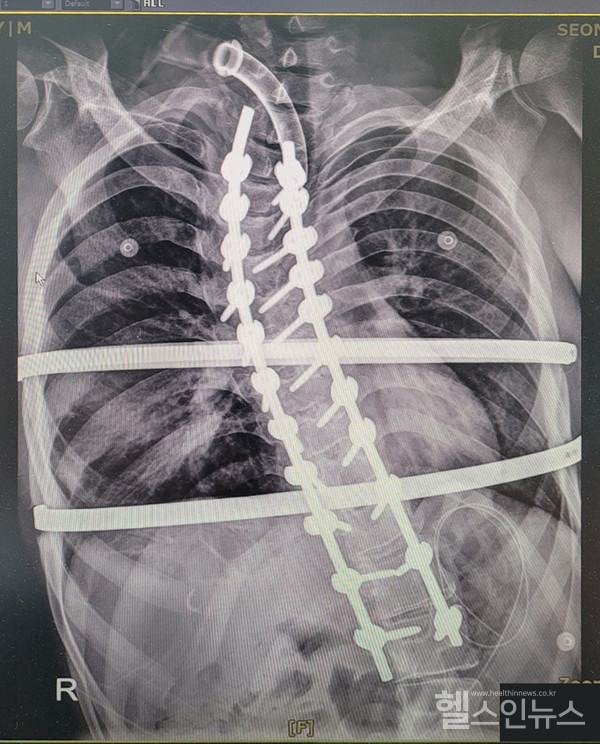

해당 환자는 척추의 만곡(휘어진) 각도가 60도 이상의 고도 변형 상태로 외형적, 기능적 건강 상태에 다양한 부작용이 초래할 수 있어 ‘고난도, 고위험’ 척추 수술이 불가피한 상태였다.

4,000례 이상의 척추 수술을 집도한 서남병원 정형외과 장영수 진료부원장은 “특발성 척추측만증을 앓고 있던 환자로 척추의 곡선이 정상적이지 않아 호흡을 위한 흉부의 공간이 협소했다.”며 “우측 기관지가 휘어진 척추로 인해 눌린 상태가 장기간 지속되어 폐렴 등 다양한 기능상 문제가 추가적으로 발생하고 있어 척추 수술이 매우 시급한 상황이었다.”고 말했다.

이와 같이 환자의 생명을 살리기 위한 촌각을 다투는 순간 서남병원 척추 수술 명의 장영수 진료부원장과 성인 중증 척추 수술의 대가 한일병원 정형외과 김진혁 과장은 수술 과정의 안전성과 수술 후 환자의 회복 시간 단축을 위해서 전문의 2인이 동시 수술을 진행해 제한된 폐 기능을 정상 수준으로 확보하고 현재 환자는 성공적인 회복 단계에 진입한 상태다.